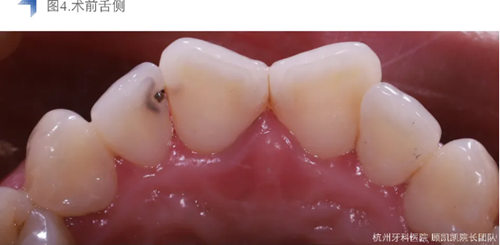

接診后口內(nèi)檢查12近中鄰面較大面積齲齒,探不適,叩無不適,冷熱測試同時對照牙及臨牙,BOP+,捫診(-),未有異常松動度。術(shù)前CBCT檢查如下圖,未見明顯根尖周透射影。

局麻橡皮障下去齲盡,極盡髓,iroot bp+蓋髓,上面覆蓋bisco硅酸鈣,流體樹脂洞型重建后貼面預(yù)備,排齦后Cerec Omincam光學(xué)取模,3D打印樹脂模型以檢查修整瓷貼面。